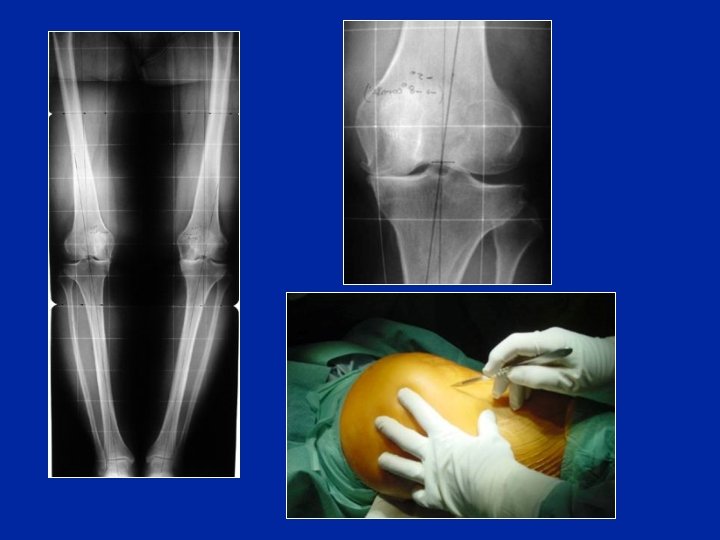

La déformation peut provenir du tibia et/ou du fémur mesurer l’angle F et l’angle T Telégoniométrie debout • • Angle HKA Angle F Angle T Bâillement F T

Dans la gonarthrose en varus la déformation siège au tibia contrairement à la gonarthrose en valgus où elle siège le plus souvent au fémur

Contrôle opératoire Contrôle radioscopique Une tige matérialisant le tibia doit passer en dedans de la tête fémorale (30 à 40 mm) 1° = 7 à 8 mm 1 - Appliquer les 2 compartiments 2 – contrôler en faisant du varus forcé

Contrôle opératoire de la correction 35 mm 5° = 35 mm On peut matérialiser le centre du fémur par un répère métallique placé sur la peau sous radioscopie, ainsi qu’un autre répère correspondant au but à réaliser Préop On peut les percevoir sous les champs opératoires Postop